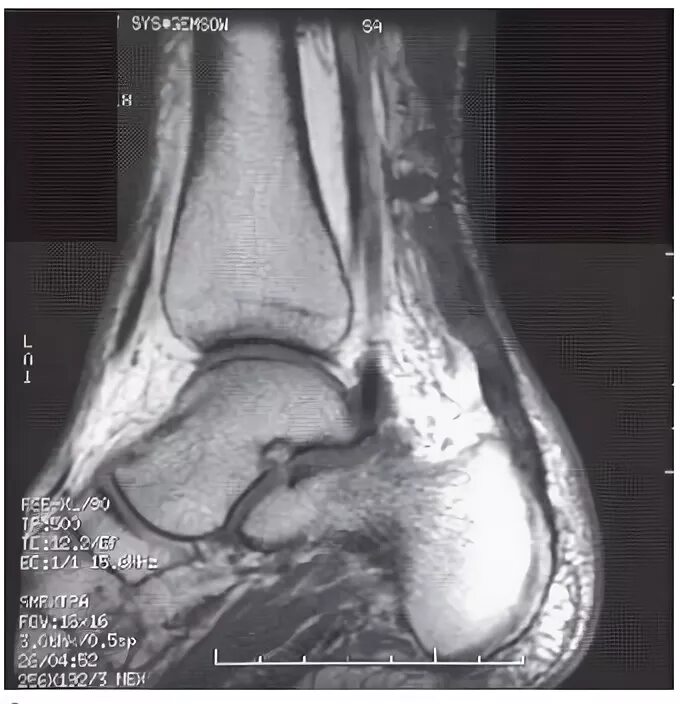

Мрт ахиллового сухожилия